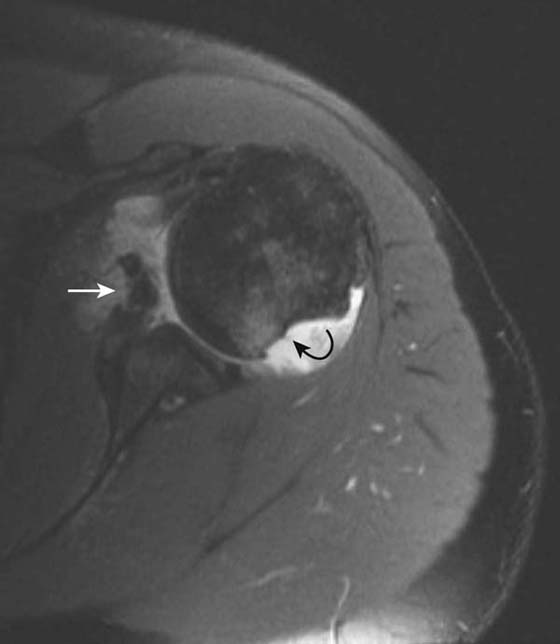

Radiography is useful in defining osseous alignment at the glenohumeral joint and may demonstrate a Hill–Sachs or bony Bankart’s lesion. CT also has utility in the assessment of osseous structures after subluxation/dislocation, particularly in evaluation of a subtle Bankart’s fracture with an equivocal MRI or intra-articular osseous fragments.21 CT is useful as a preoperative exam to assess fragment size and displacement. MR arthrography is the most sensitive test for evaluation of most of the causes, manifestations, and sequellae of glenohumeral instability.22-24 It allows for precise evaluation of the capsulolabral and ligamentous complex. Labral tears are diagnosed when intra-articular contrast material tracks into or underneath the labrum. Noncontrast MRI is also very sensitive, although use of a high-field scanner (≥0.7 T) is recommended. Labral tears most commonly associated with instability are anteroinferior or posterior (Fig. 14-9). Superior labral tears that track anterior to posterior (SLAP tears) are well seen with MR arthrography but are not usually associated with instability25,26 (Fig. 14-10). Tendon tears that can be associated with instability, including tears of the long head of the biceps tendon or subscapularis, are also well seen by MR arthrography and noncontrast MRI. Multidirectional instability typically shows no abnormality on imaging modalities, although capacious recesses may be observed.

images

Figure 14-9 Bankart’s and Hill–Sachs lesions. Axial T1 fat-saturated MRI after administration of intra-articular gadolinium (direct MR arthrogram) demonstrates sequelae of anterior shoulder dislocation. The anteroinferior labrum and bony glenoid has been disrupted (white arrow) consistent with a bony Bankart lesion. A bony defect is also seen at the posterior humeral head (curved black arrow) consistent with a Hill–Sachs lesion.